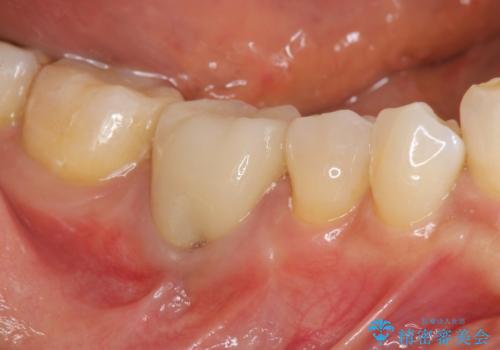

目立っていた銀歯が自然な白い歯となり、長年のコンプレックスが解消されたと満足いただくことができました。